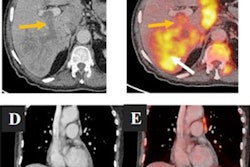

An example of PET/CT imaging from the study of a cancer patient who received the Pfizer-BioNTech COVID-19 vaccine showing FDG radiotracer uptake in the shoulder (left) and axial lymph node activity in the fused PET/CT image (right). Image courtesy of Dr. Mehemet Adin.According to the analysis, patients receiving the Pfizer-BioNTech and Moderna vaccines had similar incidences of reactive axillary lymph nodes in the first 20 days after the second dose (44% for the first 10 days for both groups, and 26% vs. 20% for days 10 to 20). However, Moderna recipients had higher incidences after 20 days than patients who received the Pfizer-BioNTech vaccine (4% vs. 15%).